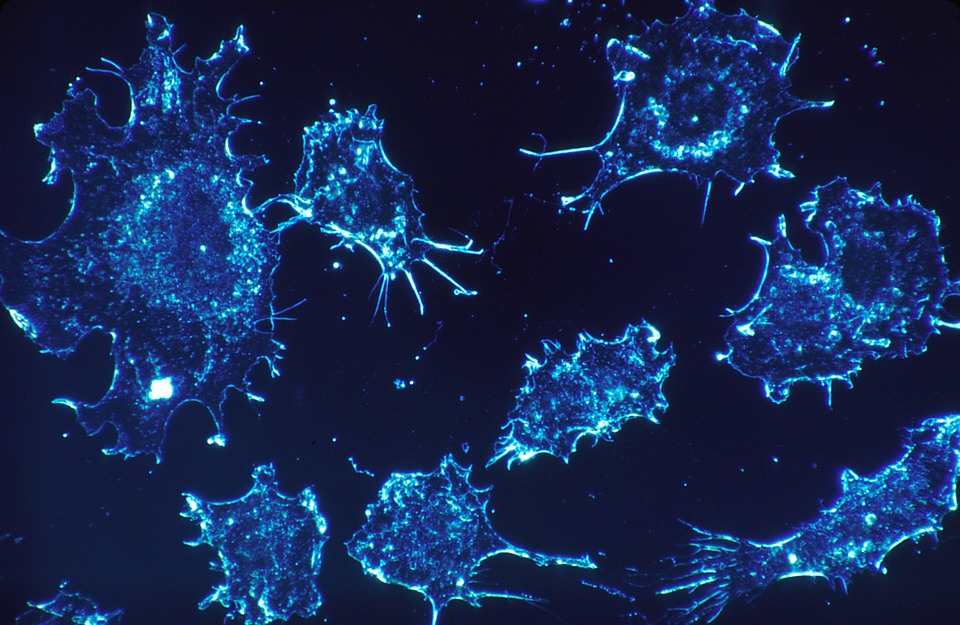

Le corps des êtres vivants tels que des animaux et des hommes possède une incroyable quantité de cellules, environ 100 000 milliards au total. Par conséquent, il est en état de renouvellement cellulaire permanent, à partir de la naissance jusqu’à la mort. Il est en quelque sorte constamment remis à neuf.

Pratiquement tous les organes, tous les tissus et toutes les cellules sont soumis à ce renouvellement cellulaire permanent et vont être complètement régénérés plusieurs fois dans une vie, à une fréquence plus ou moins élevée en fonction des cellules. Ce qui fait qu’au bout du compte, l’immense majorité des cellules et des organes sont plus jeunes que l’individu lui-même.

Ce vaste écosystème cellulaire – qui est finalement notre organisme – contient environ 250 types de cellules différentes. La grande majorité est soumise au renouvellement cellulaire, sauf quelques exceptions, comme, par exemple, les neurones et les cellules cardiaques où le renouvellement est très lent ou quasi inexistant.

Faisons un petit tour dans ce monde fascinant qui nous donne une meilleure compréhension des cellules, de notre corps, mais également des pathologies qui peuvent en résulter.